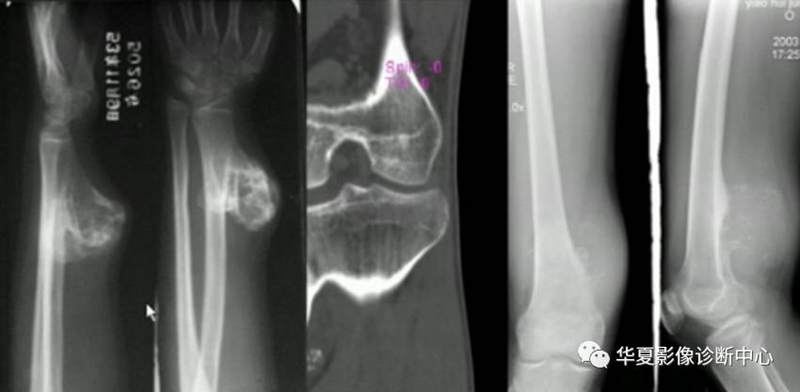

4、肿瘤软骨钙化

形态:环状,弧状,点状具有诊断意义,大小,良性者形态完整,境界清楚,密度均匀。恶性者相反。(如下图)

6、软组织改变

良性受压推移,恶性软组织肿块。(如下图)

主要有纤维源性、软骨源性及成骨源性肿瘤。

纤维源性肿瘤

软骨源性肿瘤

成骨源性肿瘤